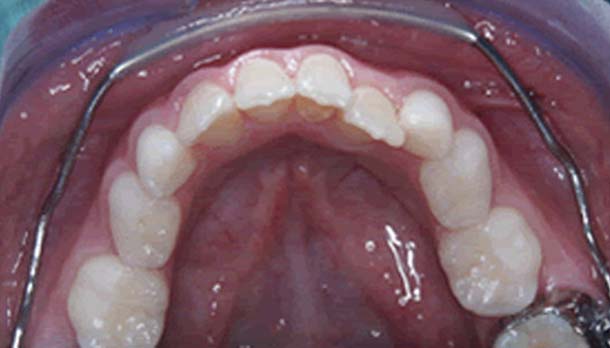

La diagnosi di malocclusione viene fatta attraverso uno studio del caso che ci consente una corretta programmazione del piano di trattamento il quale, nel caso del bambino, verrà esposto possibilmente ad entrambi i genitori. FOTO